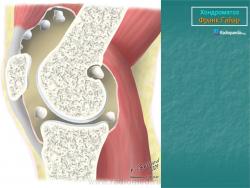

Первичный синовиальный хондроматоз

http://radsource.us/primary-synovial-chondromatosis/

1a1.jpg1a

1b.jpg

1c.jpg

Рисунок 1: